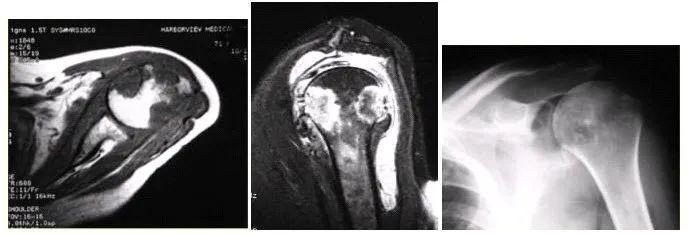

肩袖损伤

由于慢性积累性劳损或者一次急性损伤导致肩部疼痛,伴有主动活动时明显疼痛。主动活动受限明显,但被动活动影响不明显。需要肌骨超声或者肩部MR 确诊。

肩部肿瘤、结核

疼痛起病时间长,进展缓慢,夜间疼痛加重,伴有体重减轻,低热等需排除肩部肿瘤、结核等。